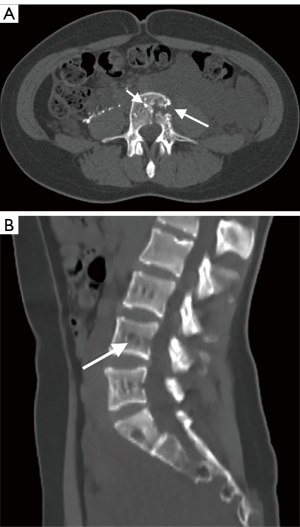

The involvement locations and incidence of bone lesions in 39 cases are detailed in Table 2. According to the morphology of bone lesions, these were divided into the following four types: (I) cystic changes (n=30; Figure 2), which showed single or multiple round-like cystic hypodense shadows in bone. The lesions had clear borders with or without sclerotic margins, and the maximum diameter was less than 5 cm. Marginal sclerotic margins (n=28), with one case showing iodized oil deposits within the lesion. (II) canal-like or honeycomb-like changes (n=34; Figure 3), which showed a tortuous, tubular distribution of hypointense shadow with clear margins and continuous at multiple levels above and below. The bone cortex was smooth or irregularly fractured in a worm-like pattern, while lesions were seen in 20 cases with iodized oil deposits. (III) Osteoporosis-like changes (n=16 cases; Figure 4), which showed a diffuse decrease in bone density and thinning of bone trabeculae. No lipiodol deposition was seen in any of the 16 cases in this group. (IV) Osteosclerosis-like changes (n=8; Figure 5), with two cases showing smooth thickening of the bone cortex, three cases showing increased density of osteophytes in the medullary cavity, three cases showing mixed presence, and five cases showing narrowing of the medullary cavity. Iodized oil deposition was not observed in any case.